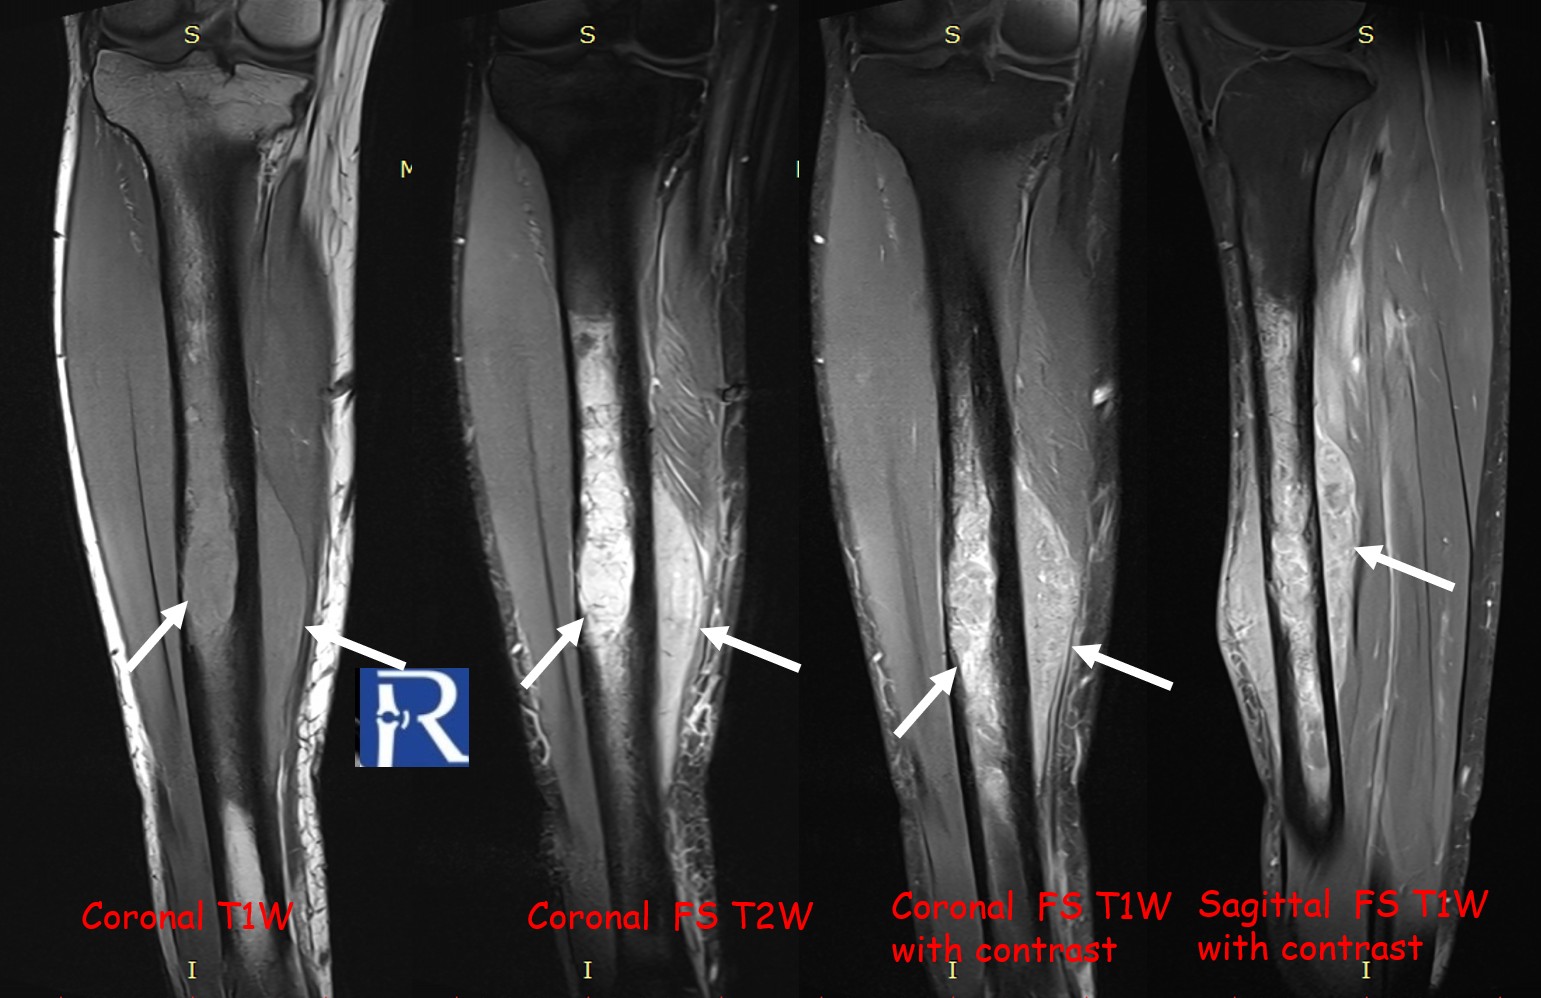

MRI revealed a significant soft-tissue component extending beyond the cortical margin, appearing hypointense on T1-weighted and intermediate on T2-weighted sequences, with heterogeneous contrast enhancement.

Diffusion-weighted imaging (DWI) showed marked diffusion restriction in both osseous and soft-tissue components, reflecting high cellularity.

The lesion exhibited limited cortical destruction, yet extensive soft-tissue extension. Multiple conglomerate inguinal and pelvic lymph node enlargements were also identified, demonstrating signal characteristics similar to those of the primary lesion.

These imaging findings—particularly the absence of periosteal reaction, intermediate T2 signal, and marked DWI restriction—favored the diagnosis of lymphoma over Ewing sarcoma.